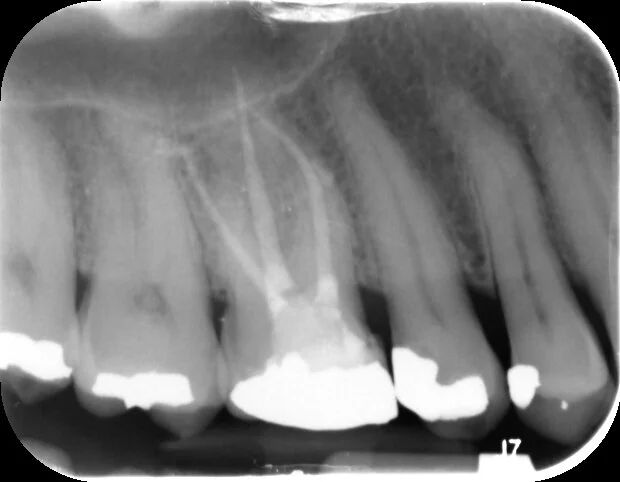

A suboptimal root filling on the UR6

Post treatment with all canals filled with a good coronal-apical seal